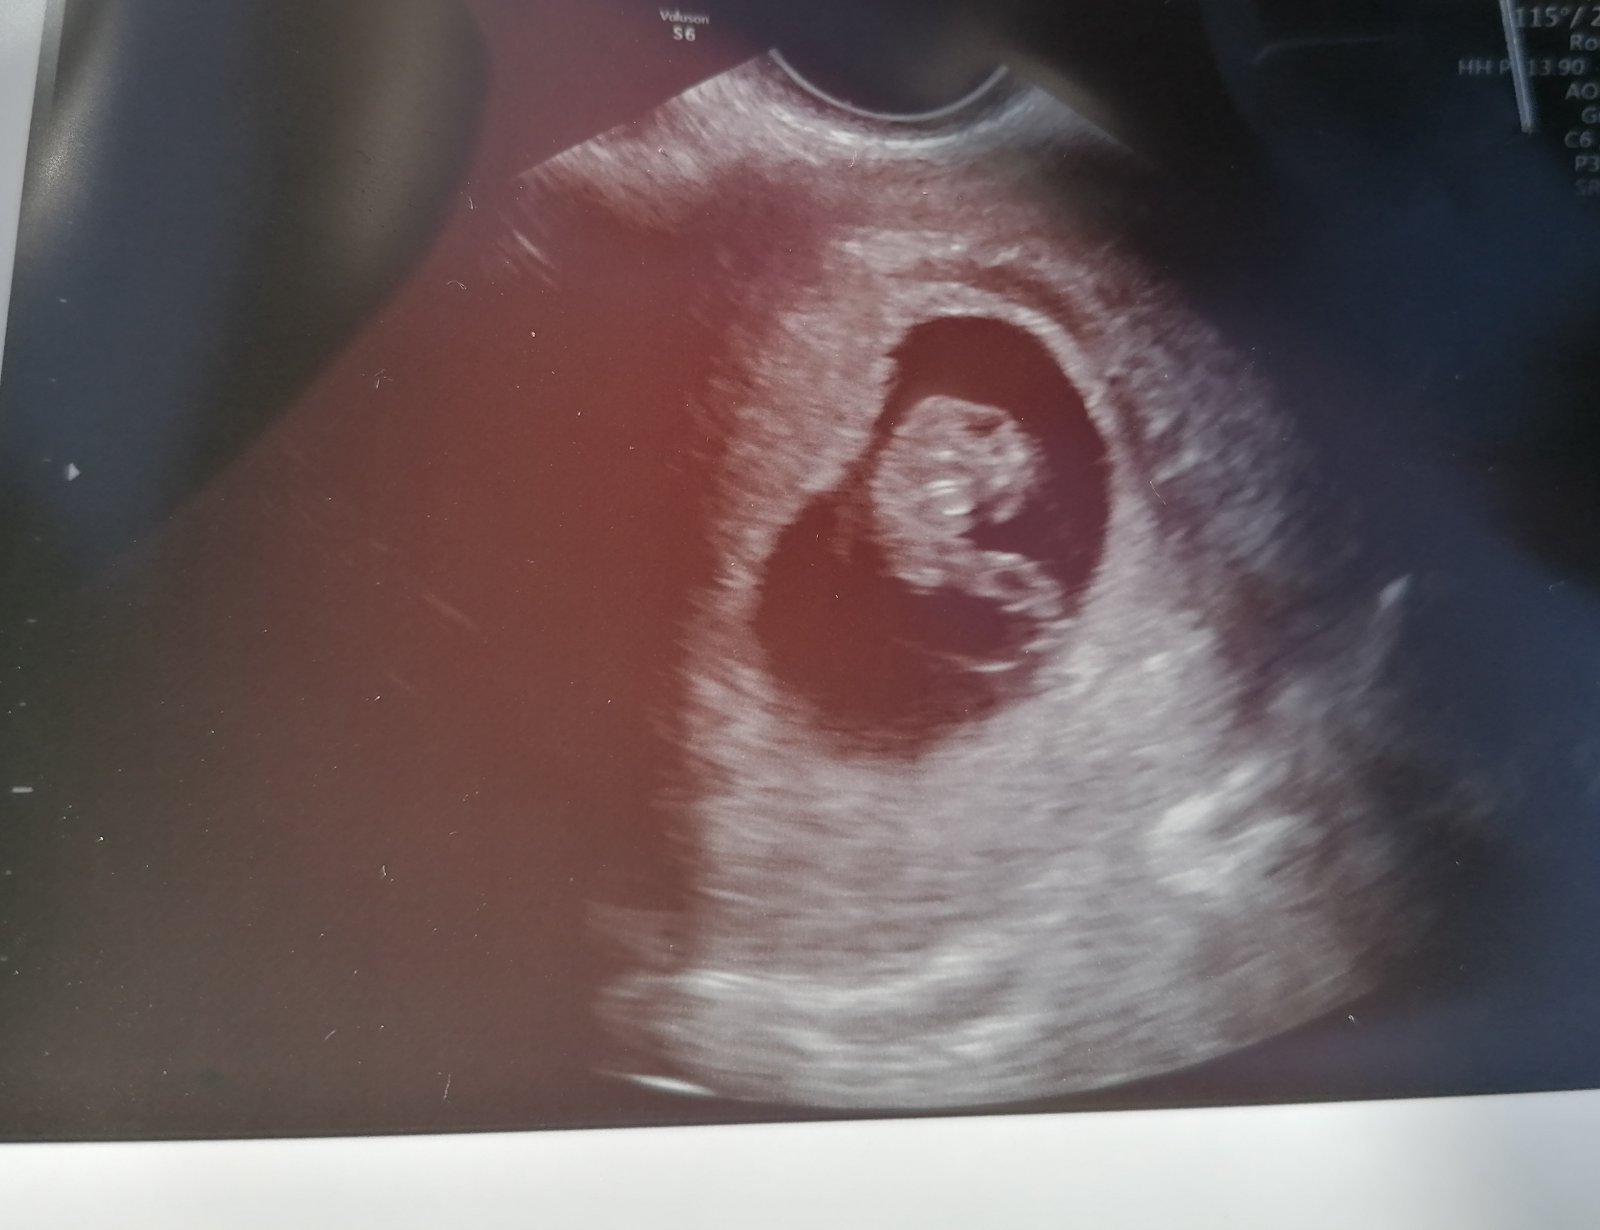

@hafanana25 ahooj no ako pokračuješ? 🙂 Ja som sa trosku odmlacala nakoľko som mala problémy s krvácaním, v podstate ešte aj mam. Špinenie mam nonstop a 2x sme utekali na pohotovosť kvôli silnému krvácaniu. Srdiečko stále bilo a zatiaľ vyzerá napriek všetkému všetko ôk. Našli mi hematom ktorý ale nieje prichytený o plodovy vak tak by vraj nemal bábätku uškodiť. Mam prikázane ležať tak už asi 3 týždne nič iné nerobím. Včera sme boli na kontrole a už som krásne počula srdiečko, maličké ma 1,5cm a vyzerá trosku ako švábik😅na foto sme v 7tt+6